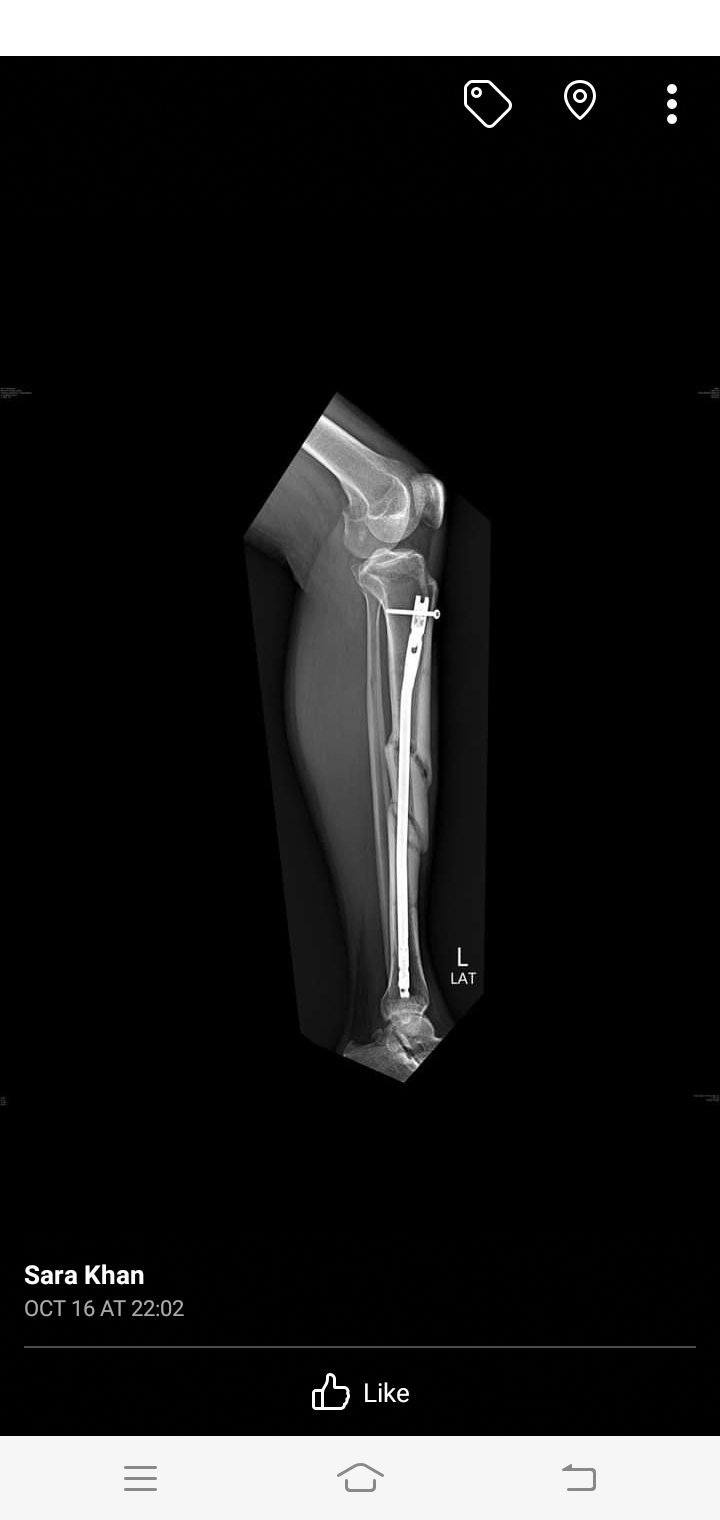

aoa please dr tell me when it will b healed . 5 march 2023 opreation . now october how many time to take to heel completly . age patient 47 years. patient got accident in january both legs are damag right leg is most damage and then in feb right leg amputed above knee . this is left leg x ray . want to ask how many time to take heeling completly. please tell me in how many time to take complete heeling

Xrays show good healing. Is the patient walking? Ask the patient to walk stick or crutch on right side. The more the patient walks on this left leg, the better remodeling there wiil be. In short, patient can walk on left leg

your injury is a severe and operation done very well you start to weight beering on th injured leg wait 18 to 24 months for full recovery